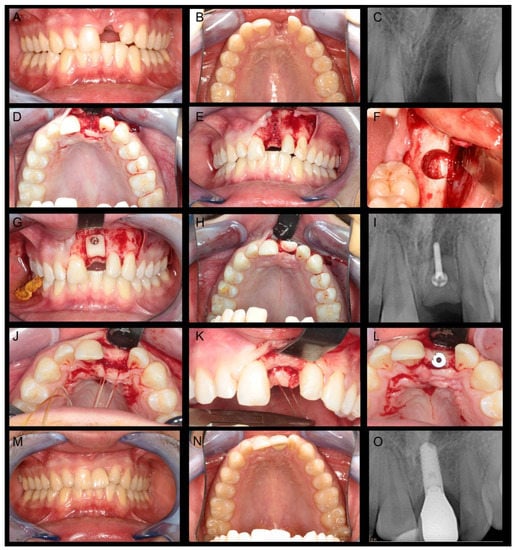

In a period of almost 13 years, a total of 54 patients with 64 bone cylinders were surgically treated with the here described standardised bone transfer. Fifty-two patients completed the questionnaire, and 48 (92.3%) agreed to clinical follow-up consultations, where 49 bone transplantation sites could be observed. Figure 2 outlines the clinical course of a patient with bone atrophy in the left maxillary central incisor region who was treated with a standardised bone graft from the left retromolar region of the mandible.

Figure 2. Clinical case report of patient with bone atrophy in the left maxillary central incisor region: (AC) Intraoral photos and radiograph show the initial situation; (D,E) intraoperative photos shows bone defect; (F) intraoperative photos after the removal of the standardised bone graft from the left retromolar area of the mandible; (GI) Intraoperative photos and radiograph after bone graft fixation using micro-lag-screw; (JL) Intraoperative photos 3 month show the bone healing and implant insertion; and (MO) intraoral photos and radiograph after prosthetic rehabilitation using ceramic crown.